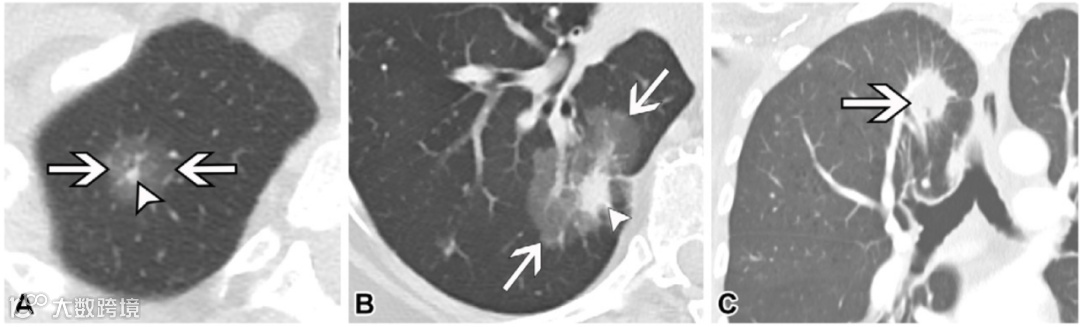

图1. 三例T1期肺癌患者。

(A)76岁男性的轴位非增强胸部CT图像(肺窗),显示右上叶部分实性腺癌(箭头)。整体直径(箭头之间)为1.5厘米,实性成分(短箭头)仅为0.4厘米,符合临床T分期描述为T1(mi)。在部分实性结节中,由于实性成分与侵袭性癌症的相关性更强,因此在分期时使用实性成分,而整体直径仅作为记录。

(B)74岁女性的轴位非增强胸部CT图像(肺窗),显示右下叶部分实性腺癌(箭头),整体直径为4.5厘米(箭头之间),实性成分(短箭头)为1.5厘米,符合临床T分期描述为T1b。

(C)61岁女性的冠状重建非增强胸部CT图像(肺窗),显示右上叶实性腺癌(箭头),大小为2.4厘米,符合T1c期。